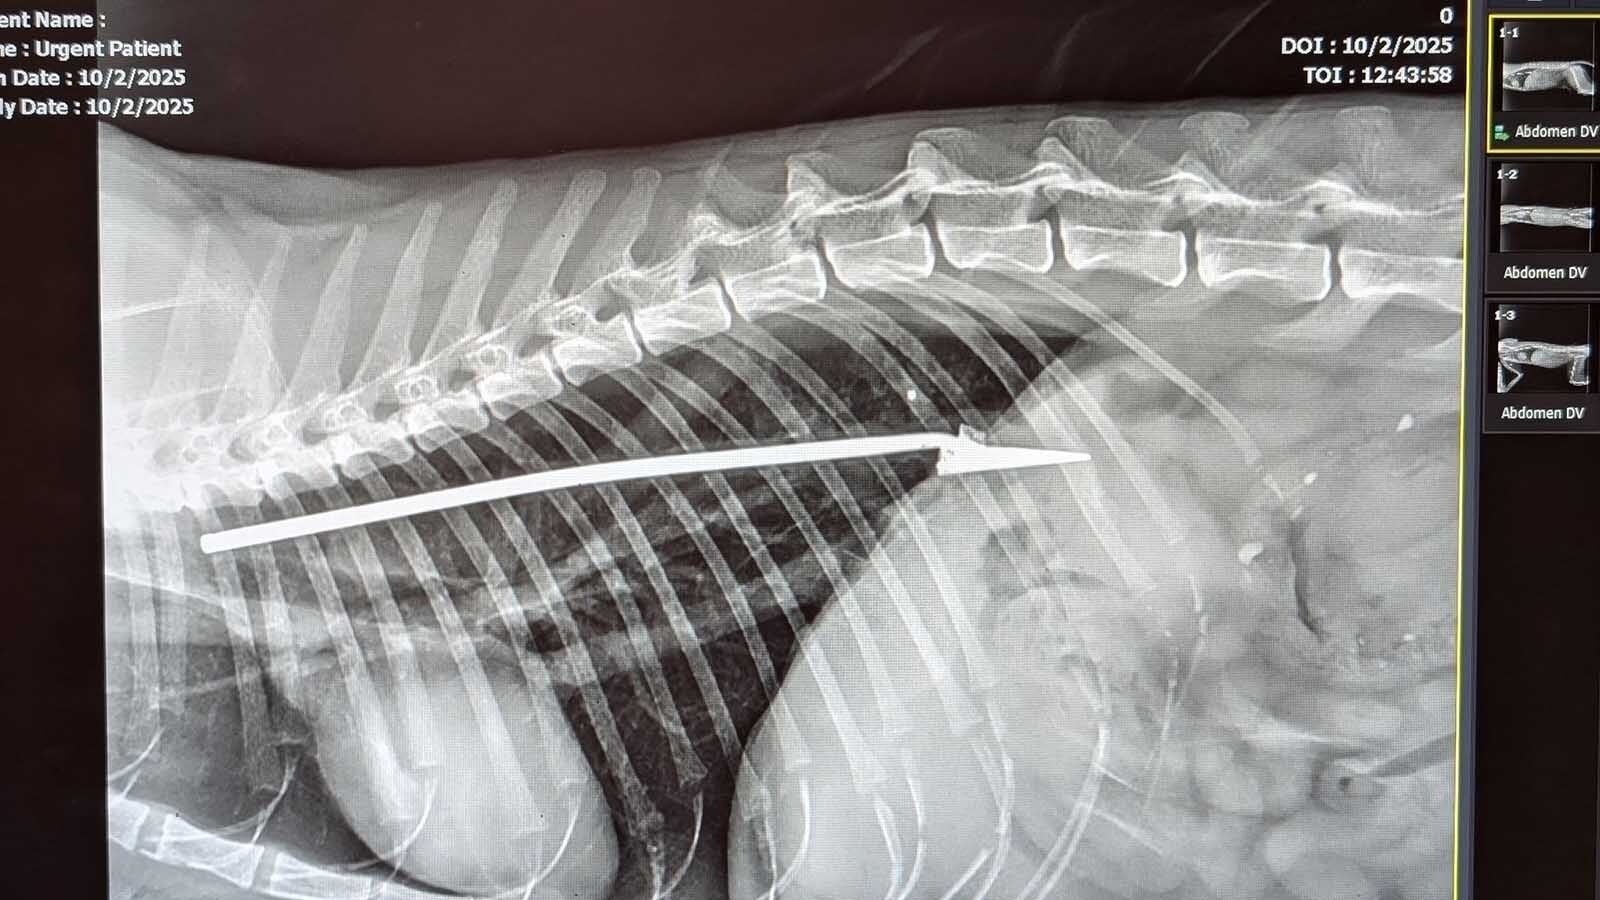

There was a large, arrow-shaped piece of metal lodged within the cat’s rib cage, sitting right between its heart and lungs.

“This thing was about 5 inches long,” Fabian said. “And I don’t know how that cat was functioning.”

The X-ray also discovered a bullet lodged in the cat’s shoulder, whether that happened during the same incident or another, it’s impossible to tell.

Even though the arrow had missed its heart and lungs, the cat’s ribs had been broken by the blow dart.